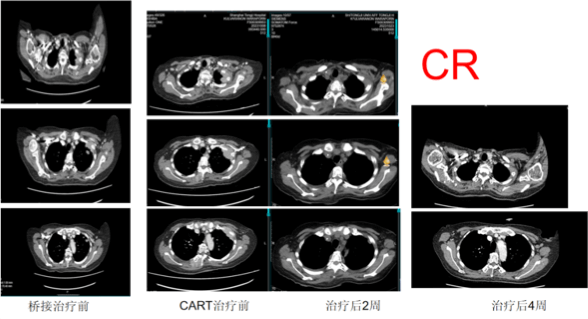

Tumors Completely Disappeared in 22 Days! CAR-T Treatment Sets Survival Miracle

What shocked everyone was that the examination results 22 days after CAR-T treatment showed that Ms. M had achieved hematologic CR, meaning that no cancer cells were detected in her blood. Her pain and anemia were also reversed. It was simply a miracle!